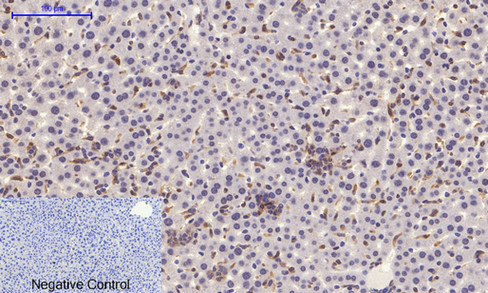

产品名称Stat1 (phospho Tyr701) Rabbit Polyclonal Antibody

推荐应用IF-P,IF-F,IF-ICC,WB,IHC-P,IP,ELISA

特异性Phospho-Stat1 (Y701) Polyclonal Antibody detects endogenous levels of Stat1 protein only when phosphorylated at Y701.

稀释度IF-P/IF-F/IF-ICC 1:50-200, WB 1:500-1:2000, IHC-P 1:100-1:300, Immunoprecipitation 2-5 ug/mg lysate, ELISA 1:10000.Not yet tested in other applications.